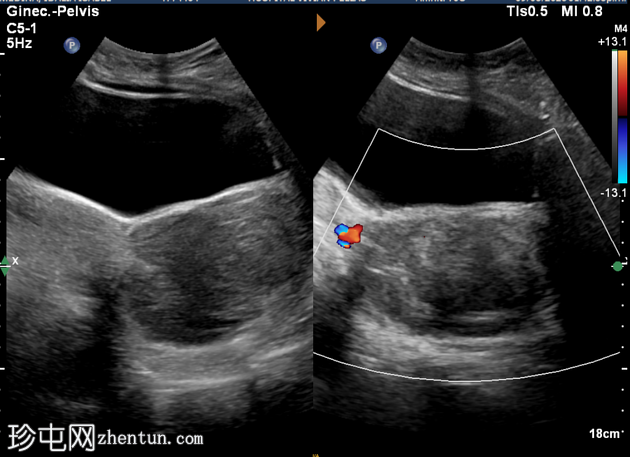

2.png

纵切面

子宫前倾位。纵径、前后径、横径分别为145 × 41 × 58 mm。

由于存在一个边界清晰、形态不规则的低回声实性肿块,子宫呈异质性回声。该肿块位于宫颈区域,似乎延伸至阴道方向,大小为93 × 69 × 59 mm。

超声检查发现宫颈区域有一实性异质性肿块,延伸至阴道。鉴别诊断包括宫颈平滑肌瘤和宫颈肿瘤。需行盆腔MRI检查以明确病变性质。